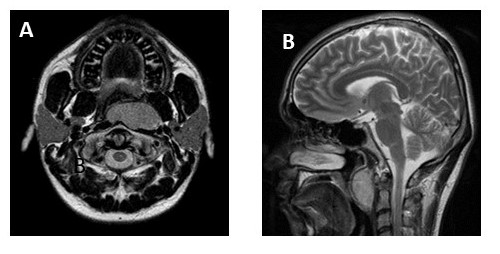

Dentro de los estudios de imagen presenta tomografía de cuello con contraste endovenoso en la cual se aprecia imagen hipodensa difusa que compromete la pared lateral izquierda de orofaringe con un diámetro de 4,28 cm x 2,83 cm, que disminuye la luz de la orofaringe y con realce heterogéneo luego de la administración del contraste, sin ganglios patológicas (Figura 3). En RMN de cuello se evidencia lesión sólida, en pared posterior de orofaringe con obliteración de la luz, de 4,3 cm x 3,71 cm, infiltrando fascia prevertebral y músculos prevertebrales adyacente a cuerpo vertebral de C2 (Figura 4). Estudios de extensión pulmonar y hepático sin lesiones sugestivas de metástasis.

En tomografía de cuello con contraste endovenoso posterior a quimio/radioterapia, se aprecia tumor aspecto heterogéneo y densidad sólida en orofaringe, sin evidencia de infiltración del espacio prevertebral ni de estructuras óseas adyacentes, sin adenomegalias. En RMN con contraste de cuello se visualiza lesión que capta contraste localizado en la pared faríngea posterior que mide 3,8 cm x 1,9 cm, impresiona tener planos de clivaje con estructuras adyacentes, sin infiltración de espacio prevertebral, que al comparar con estudio previo, se determina reducción de tamaño de lesión (Figura 5).